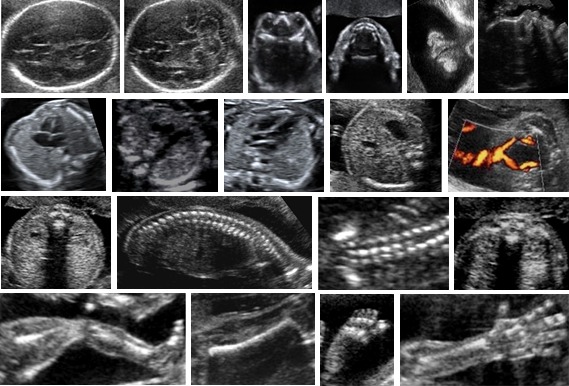

Strukturální vady orgánů a systémů plodu je možno rozpoznat pouze prostřednictvím zobrazovacích metod, respektive ultrazvuku a v indikovaných případech i magnetické rezonance. V žádném případě není možno strukturální vady diagnostikovat provedením invazivního výkonu (amniocentézy a podobně).

U všech těhotných žen se proto provádí v polovině těhotenství, tedy okolo 20. týdne gravidity, ultrazvukový screening vrozených vad plodu, při kterém může zkušený lékař detekovat přibližně devadesát procent vrozených strukturálních vad. Protože se plod během těhotenství neustále vyvíjí, měla by být základní kontrola jeho anatomie a morfologie vždy připojena i při standardním ultrazvukovém vyšetření okolo 30. týdne těhotenství.

(Foto: MUDr. Veronika Frisová, Profema)

Díky rozvoji ultrazvukové techniky se diagnostika strukturálních vrozených vad postupně přesouvá i do časnějších stadií těhotenství a v současné době je již v prvním trimestru těhotenství (11. až 14. týden) možno rozpoznat přibližně padesát procent strukturálních vrozených vad. Výhodou časné diagnostiky vrozené vady je v případě její velmi špatné prognózy mnohem jednodušší možnost ukončení těhotenství, která spočívá v krátké operaci v celkové narkóze (vyprázdnění obsahu dutiny děložní speciálním nástrojem přes pochvu). Pokud je závažná vrozená vada plodu diagnostikována po 14. týdnu těhotenství a těhotná žena se rozhodne ukončit těhotenství, musí bohužel potrácený plod po vyvolání děložní činnosti klasicky porodit.